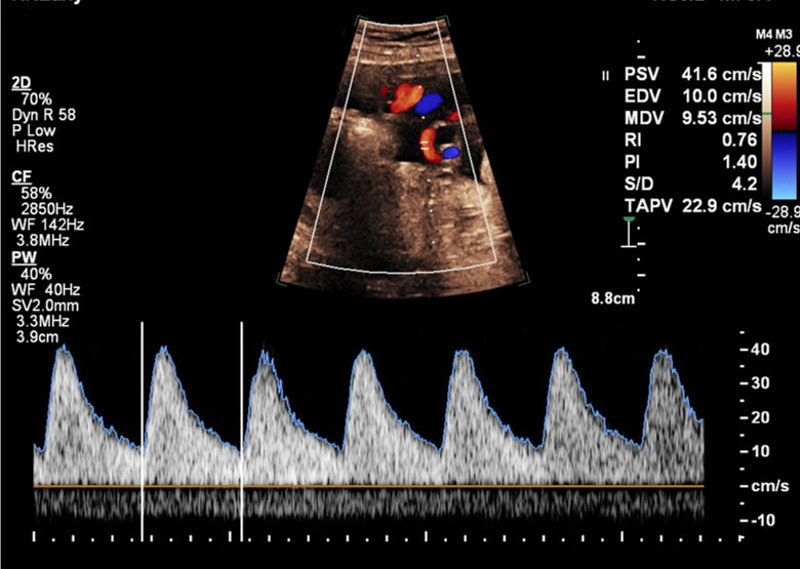

Doppler-Abschlusskurs

von 25. November bis 26. November 2022

Tübingen, Universitätsfrauenklinikum

A5/2022 - Dopplersonografie Kursreihe 2022